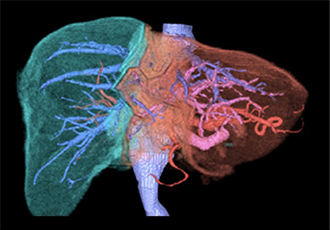

図2 VINCENTによるシミュレーション画像

肝臓や脈管の3次元的な描出が可能です。

肝臓の門脈がピンク色に、肝静脈が青色に、肝転移巣が緑色に描出されています (A)。

さらに肝切除予定領域が緑色と黄色で示されています (B)。